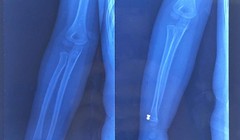

Hình ảnh đạn súng hơi găm trong tay bệnh nhi

Hà Nội: Bé trai 5 tuổi bị đạn súng hơi găm vào tay đã ra viện

VietTimes – Ngày 31/5, BS. Phạm Xuân Hưng - Khoa Chấn thương chỉnh hình, Bệnh viện Xanh Pôn  - cho biết, bé trai 5 tuổi bị đạn súng hơi găm vào tay đã bình phục và ra viện.